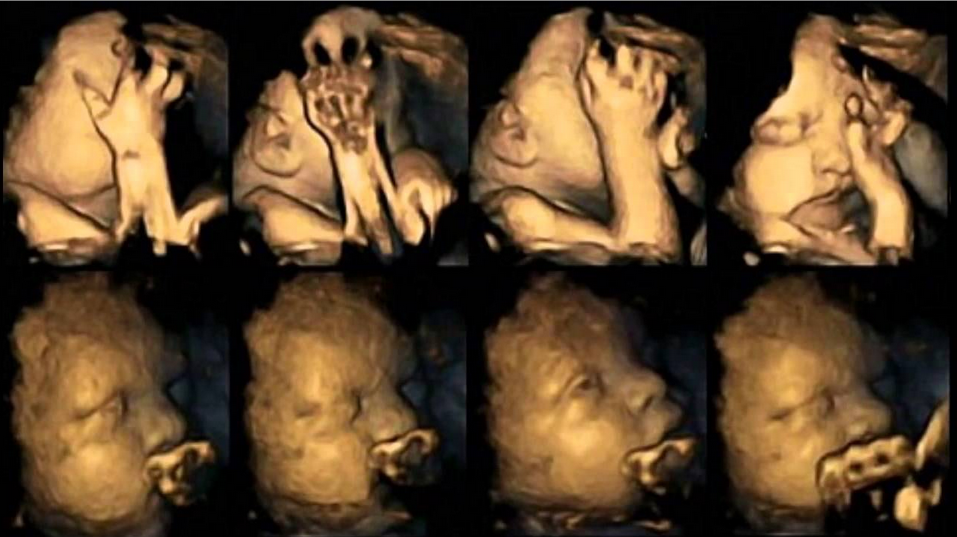

Gli effetti nocivi del fumo durante una gravidanza ripresi in 4 D. E’ il risultato di una ricerca effettuata dalla…

Che il fumo in gravidanza faccia male è noto. Il problema, in Emilia-Romagna, è che il 40,1% delle fumatrici non ha perso il vizio della sigaretta durante la gestazione.